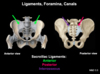

Foramen and canals of the pelvis

- The sacrotuberous and sacrospinous ligaments form what foramen?

- Obturator membrane? Canal? ?

- What do all foramen / canal form passageways to

Foramen and canals of the pelvis

- The sacrotuberous and sacrospinous ligaments form the:

-

Greater sciatic foramen

- Superior to ischial spine

- Passageway to the gluteal region

-

Lesser sciatic foramen

- Inferior to ischial spine

- Passageway to perineum

-

Greater sciatic foramen

-

Obturator membrane

- Fills the obturator foramen, except for a small opening, the obturator canal

- Obturator canal forms passageway to the medial compartment of the thigh